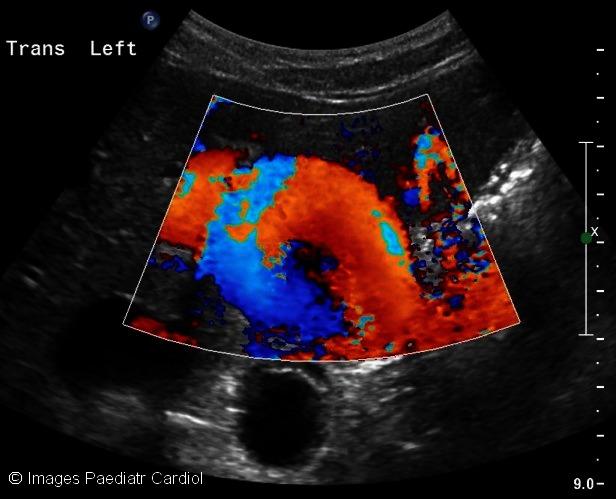

Gastric pseudoaneurysm in the setting of Loey's Dietz Syndrome.

Images Paediatr Cardiol. 2012 Jul;14(3):1-5.

PMID:23720690